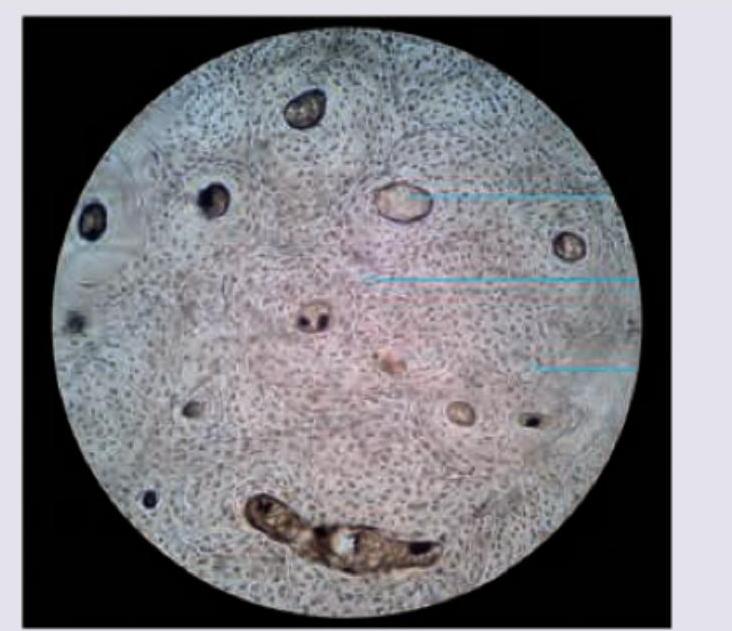

The image shows presence of:

Explanation: ***Fibrocartilage*** - The image displays characteristic features of fibrocartilage, including visible bundles of **collagen fibers** (appearing wavy and somewhat disorganized) interspersed with **chondrocytes** residing in lacunae. - The arrangement and presence of abundant collagen make it suitable for locations requiring robust **tensile strength** and **shock absorption**, such as intervertebral discs and menisci. *Compact bone* - Compact bone would typically show **Haversian systems (osteons)** with concentric lamellae surrounding a central canal, which are not evident in this image. - The cellular components, **osteocytes**, would be found within lacunae, but the overall matrix and organization are distinct from cartilage. *Hyaline cartilage* - Hyaline cartilage has a **smooth, glassy matrix** with very fine collagen fibers that are not usually visible under light microscopy, unlike the distinct bundles seen here. - Chondrocytes in hyaline cartilage often appear in **isogenous groups** (clusters of cells), which are not prominently featured in this image. *Myositis ossificans* - **Myositis ossificans** is a condition where bone forms within muscle tissue, typically following trauma, and would show mature or immature bone tissue, not cartilage. - Histologically, it would present with **osteoid formation** and calcification within muscle, along with inflammatory cells, which are absent in this image.